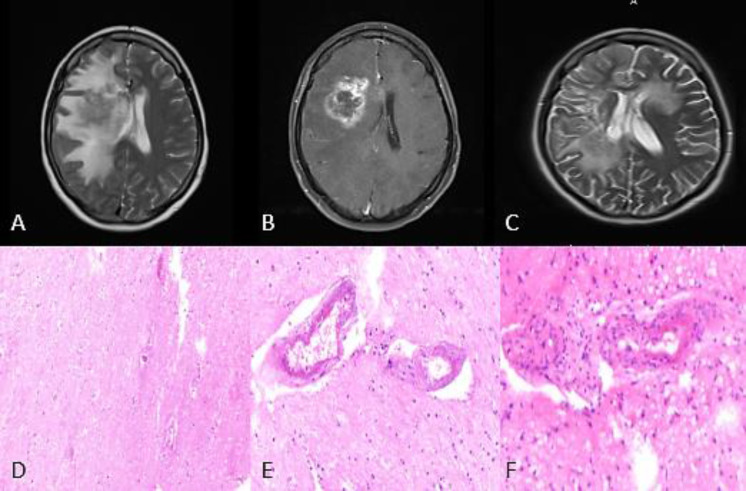

Mass-like presentation of primary angiitis of the central nervous system: A clinical note.

中枢神经系统原发性脉管炎的肿块样表现:临床记录。